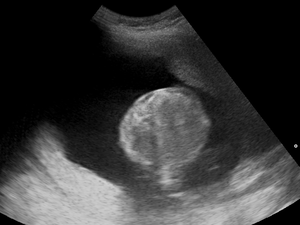

Polyhydramnios (polyhydramnion, hydramnios, polyhydramnios) is a medical condition describing an excess of amniotic fluid in the amniotic sac. It is seen in about 1% of pregnancies.[1][2][3] It is typically diagnosed when the amniotic fluid index (AFI) is greater than 24 cm.[4][5] There are two clinical varieties of polyhydramnios:

During the pregnancy, certain clinical signs may suggest polyhydramnios. In the mother, the physician may observe increased abdominal size out of proportion for her weight gain and gestation age, uterine size that outpaces gestational age, shiny skin with stria (seen mostly in severe polyhydramnios), dyspnea, and chest heaviness. When examining the fetus, faint fetal heart sounds are also an important clinical sign of this condition.